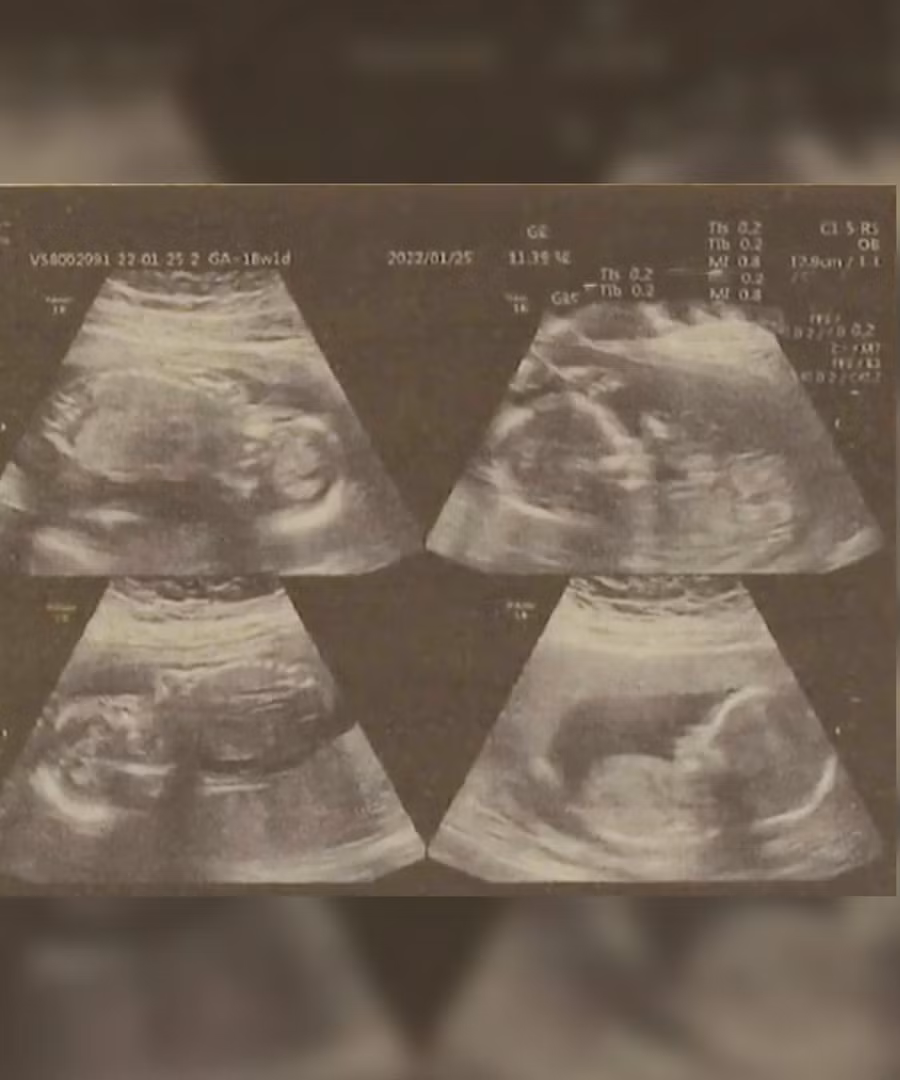

Ông Chu nói ban đầu các bác sĩ thông báo người vợ 22 tuổi của ông mang thai ba vì thai nhi thứ tư bị che khuất trong quá trình kiểm tra sức khỏe. Khi họ phát hiện em bé thứ tư thì đã quá muộn để giảm số lượng thai nhi lại.

Bác sĩ Ma cho biết thai phụ đến khám khi thai được 22 tuần tuổi và đã được cấp cứu ngay vì có vấn đề với cổ tử cung .